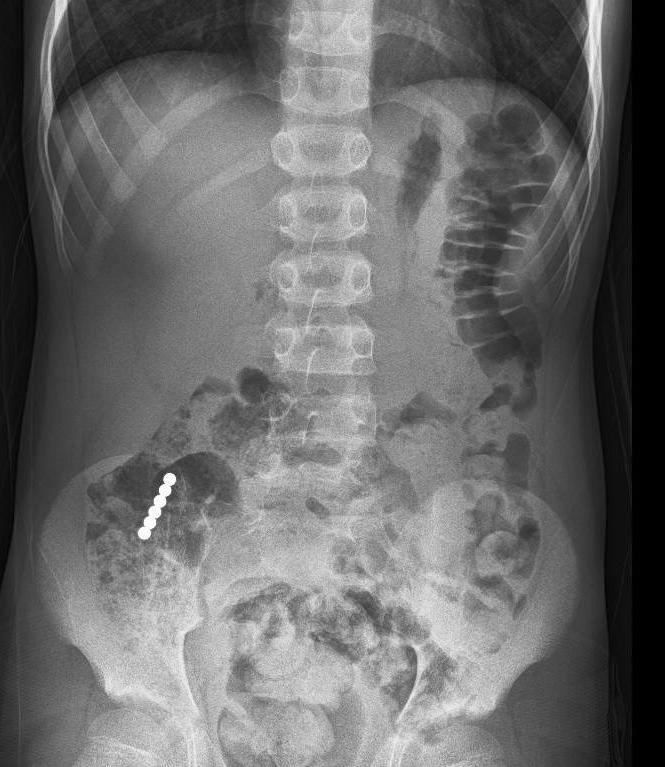

"המטופל הגיע אלינו במצב טוב וסיפר שבלע מגנטים קטנים שהיו חלק ממשחק", מתאר ד"ר סאמח טאטור, רופא בכיר ביחידה לגסטרואנטרולוגיה ותזונה בילדים ונוער בבית החולים, "במיון בוצע צילום שבו נצפו כל המגנטים באזור המעי הדק מעבר לקיבה, לכן לא בוצעה גסטרוסקופיה לשליפת הגופים הזרים".

"בשלב הראשון", סיפר הד"ר, "החלטנו לאשפז אותו להשגחה במחלקה כירורגית ילדים במטרה לאפשר למגנטים לצאת לבד ממערכת העיכול. המגנטים אכן התקדמו במערכת העיכול, אבל נתקעו בחיבור שבין המעי הדק למעי הגס. בתיאום עם הרופאים מכירורגית ילדים ובנוכחותם, הוחלט לבצע פעולת קולונוסקופיה תחת הרדמה מלאה במכון הגסטרו".